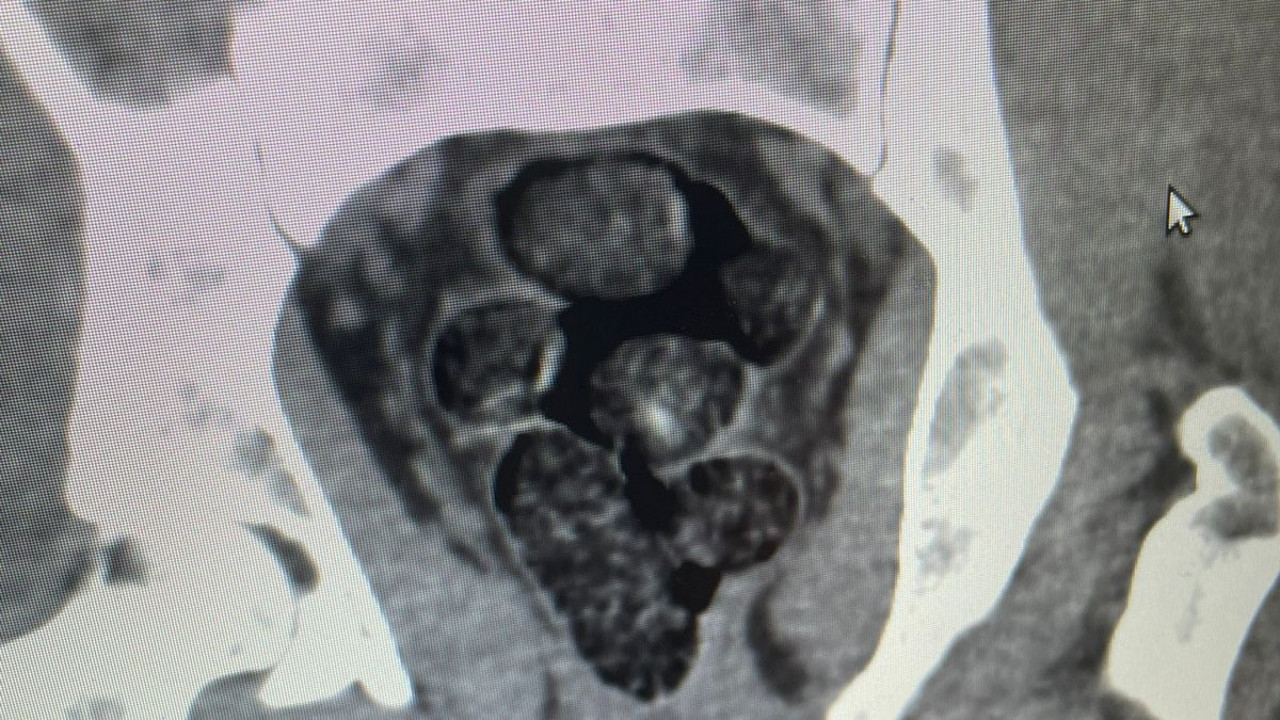

Takibe alınan şüpheli şahıs, Samsun'a iniş yaptığı sırada polis ekipleri tarafından yakalandı. Hastaneye götürülüp, tomografisi çekilen şüphelinin midesinden poşete sarılmış, 10 adet olmak üzere toplamda 191,18 gram metamfetamin ele geçirildi. Gözaltına alınan şüpheli, emniyete götürüldü.